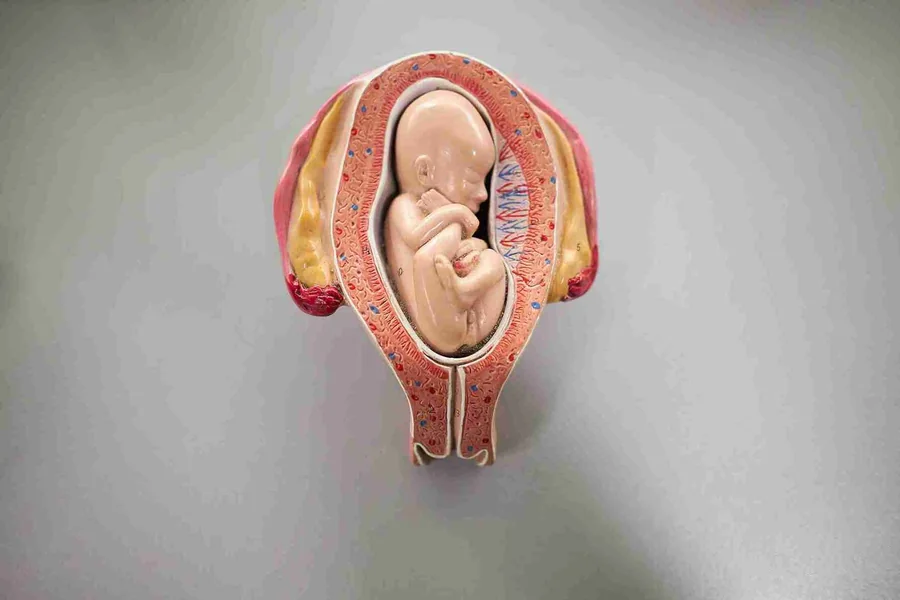

Many people in India are cautious about pregnancy, with many people investing in special rituals for the improved health of their baby. Amidst such a situation, I have seen many parents get confused with complex terms like anterior placenta. In this post, I will try to address everything related to the placenta and its positioning, so that it can be a comprehensive guide for you to understand pregnancy.

The positioning of the placenta is somewhat important in pregnancy, and in India, many people expecting a baby often go for a basic ultrasound imaging. While the procedure is not invasive, it will surely help in understanding what is going on inside.

I can clearly say that anterior positioning of the placenta does not create any immediate problems. So far as the doctor’s recommendations are concerned, this is not a problem, but has multiple benefits for the mothers.

One of the reasons why the anterior positioning is truly comfortable for the mother is that it can feel delayed. The placenta is known to cushion the movement of the baby, and I have seen that many moms in their online posts share that kicks are delayed, and when the baby grows older, the kicks are easily felt.

Although I can vouch that there are no negative impacts, anterior placental positioning may make it trickier for the doctors to feel the position of the baby. While this is not a big issue, the doctor must be careful while delivering the baby.